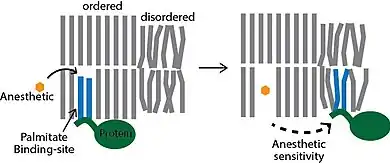

The best characterized anesthetics site accounting for the Meyer-Overton correlation resides in ordered lipid domains. Anesthetics adhere non-specifically to the surface of a palmitate specific binding site within the lipid membrane displacing the palmitate from ordered GM1 lipids. The process gives rise to a component of membrane-mediated anesthesia. [19] A similar mechanism was shown for luciferase.[20] The anesthetics bound non-specifically to a hydrophobic surface and competed out the specific binding of luciferin. However luciferase is not physiologically relevant to vertebrates as it is not endogenously expressed in vertebrates.

According to the lateral phase separation theory[28] anaesthetics exert their action by fluidizing nerve membranes to a point when phase separations in the critical lipid regions disappear. This anaesthetic-induced fluidization makes membranes less able to facilitate the conformational changes in proteins that may be the basis for such membrane events as ion gating, synaptic transmitter release, and transmitter binding to receptors. More recent techniques with super resolution imaging show that the anesthetics do not overcome phase separation—the phase separation persists. Rather saturated lipids within the phase separation can undergo a transitions from ordered to disordered which is dramatically affected by anesthetics. Nonetheless the concept of proteins moving between phase separated lipids in response to anesthetic has now been shown to be correct.[29]

Modern lipid hypothesis

There are two modern lipid hypothesis which are non-exclusionary with direct protein binding. The most recent hypothesis postulates that ordered lipids in the plasma membrane contain a structured binding site for the lipid palmitate. It is a lipid binding site within a lipid structure, not a protein structure. Proteins that contain a covalently attached palmitate (palmitoylation) are targeted to the ordered lipids through a specific lipid-lipid interaction. The binding of palmitate to the lipid domain is cholesterol dependent and the cell regulates the protein by nanoscopic localization. The anesthetics work by binding non-specifically to the palmitate binding site, which disrupts the ability of the cholesterol to bind to and sequester the protein into an inactive state. This membrane mediated mechanism was demonstrated experimentally by Pavel and colleagues in 2020. They showed the enzyme phospholipase D2 (PLD2) is anesthetic sensitive and activates the potassium channel TREK-1 through a membrane mediated mechanism. The anesthetics displaced PLD2 from ordered lipid domains allowing the enzyme to be activated by substrate presentation and activate the channel.[29][30]

Thus, according to the modern lipid hypothesis anaesthetics do not act directly on their membrane protein targets, but rather perturb specialized lipid matrices at the protein-lipid interface, which act as mediators. This is a new kind of transduction mechanism, different from the usual key-lock interaction of ligand and receptor, where the anaesthetic (ligand) affects the function of membrane proteins by binding to the specific site on the protein. Thus, some membrane proteins are proposed to be sensitive to their lipid environment. A slightly different detailed molecular mechanism of how bilayer perturbation can influence the ion-channel was proposed in the same year. Oleamide (fatty acid amide of oleic acid) is an endogenous anaesthetic found in vivo (in the cat's brain) and it is known to potentiate sleep and lower the temperature of the body by closing the gap junction channel connexion.[33] The detailed mechanism is shown on the picture: the well-ordered lipid(green)/cholesterol(yellow) ring that exists around connexon (magenta) becomes disordered on treatment with anaesthetic (red triangles), promoting a closure of connexon ion channel. This decreases brain activity and induces lethargy and anaesthetic effect. Recently super resolution imaging showed direct experimental evidence that volatile anesthetic disrupt the ordered lipid domains as predicted.[34] In the same study, a related mechanism emerged where the anesthetics released the enzyme phospholipase D (PLD) from lipid domains and the enzyme bound to and activated TREK-1 channel by the production of phosphatidic acid. These results showed experimentally that the membrane is a physiologically relevant target of general anesthetics.